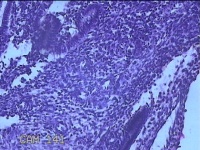

子宫颈管内膜

性别

女

年龄

42岁

临床诊断

子宫内膜息肉 瘢痕子宫

一般病史

发现宫腔息肉4个月。

标本名称

大体所见

灰白粉红色不规则碎组织0.7x0.5x0.3cm一堆。